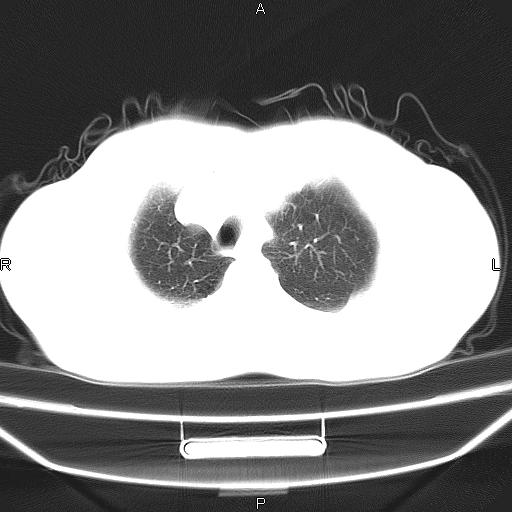

患者,男。50岁。近几日有咳嗽症状,无其他不适,既往病史无,考虑膈疝。请前辈们看看指导指导。

膈膨升,左下肺通气不良,膈肌好像还完整。

考虑左侧膈疝。

左侧膈疝。

符合隔膨升,膈肌较完整。